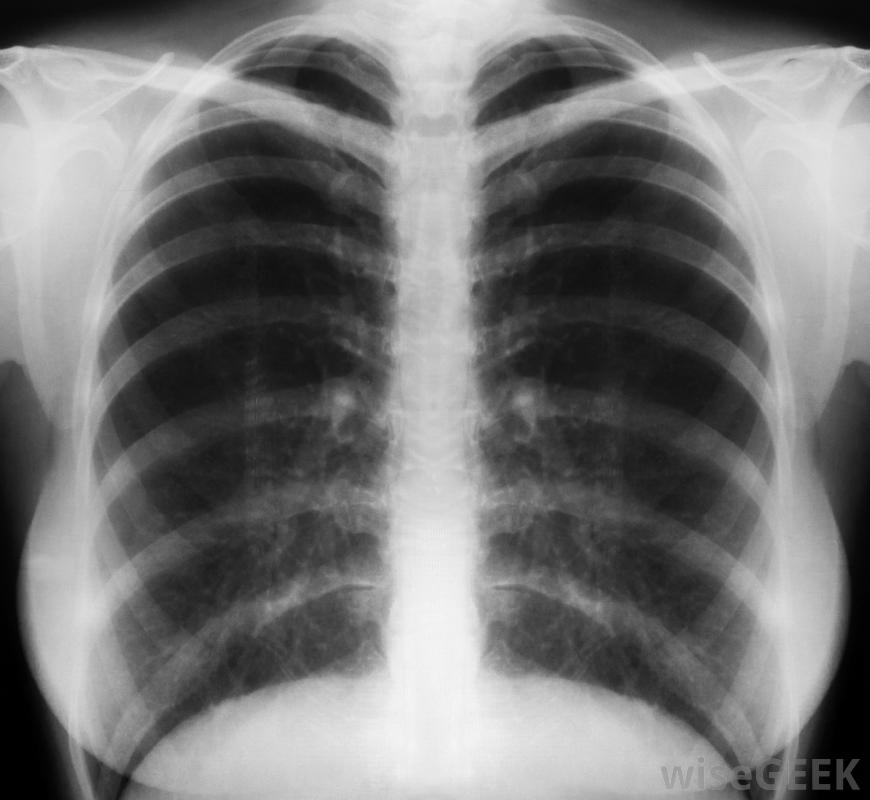

支氣管炎是一種肺部通道內壁發炎的疾病,可引起呼吸困難、氣喘、胸悶、咳嗽、發燒和疲勞等癥狀。通常由病毒引起,但也可能是細菌感染或接觸環境刺激物所致,尤其是香煙煙霧。在診斷支氣管炎之前,醫生通常會詢問病人的癥狀,然后傾聽病人的呼吸。醫生也可以做一些檢查,以確定支氣管炎的病因,并排除其他與肺部有關的疾病。這些檢查可能包括粘液分析、胸部x光檢查,胸部x光片可以幫助診斷支氣管炎,診斷支氣管炎的第一步是醫生和病人討論病人的癥狀。病人通常會被要求列出他所經歷過的任何癥狀。通常,醫生也會把聽診器放在病人的胸前,傾聽是否有異常的呼吸聲。在很多情況下,這些簡單的步驟就是診斷支氣管炎所需的全部步驟。當支氣管發炎時,會產生粘液,個體會遇到困難呼吸如果支氣管炎是由細菌感染引起的,抗生素是最有效的治療方法,但是抗生素對較常見的病毒性支氣管炎是無效的,因此,如果醫生診斷出支氣管炎,但懷疑是細菌性的,她可以分析粘液樣本。如果在病人的粘液中檢測到細菌,她可以開一個療程的抗生素藥物。胸部不適可能是支氣管炎的癥狀有時醫生可能不能立即確定病人的呼吸困難是由支氣管炎還是其他與肺有關的疾病引起的,在排除其他疾病的可能性之前,她可能會避免做出支氣管炎的診斷。為了消除其他潛在疾病,她通常會進行一次或多次診斷性檢查。這些檢查通常包括胸部X光片和肺功能檢查胸部X光片給醫生提供了病人肺部的圖像,通過研究這張圖像,醫生可以確認她對支氣管炎的診斷是正確的,反之,她可能會發現病人的肺部和胸部不適實際上是由另一種疾病引起的,如肺炎另一種通常用于確認支氣管炎診斷的測試是肺功能檢查,技術上稱為肺功能測試(PFT),病人吸入一個測量肺部吸氣和呼氣能力的裝置。肺功能差可能表明患有慢性呼吸道疾病,如哮喘或肺氣腫。吸煙會損害肺部和增加一個人患嚴重疾病的風險。